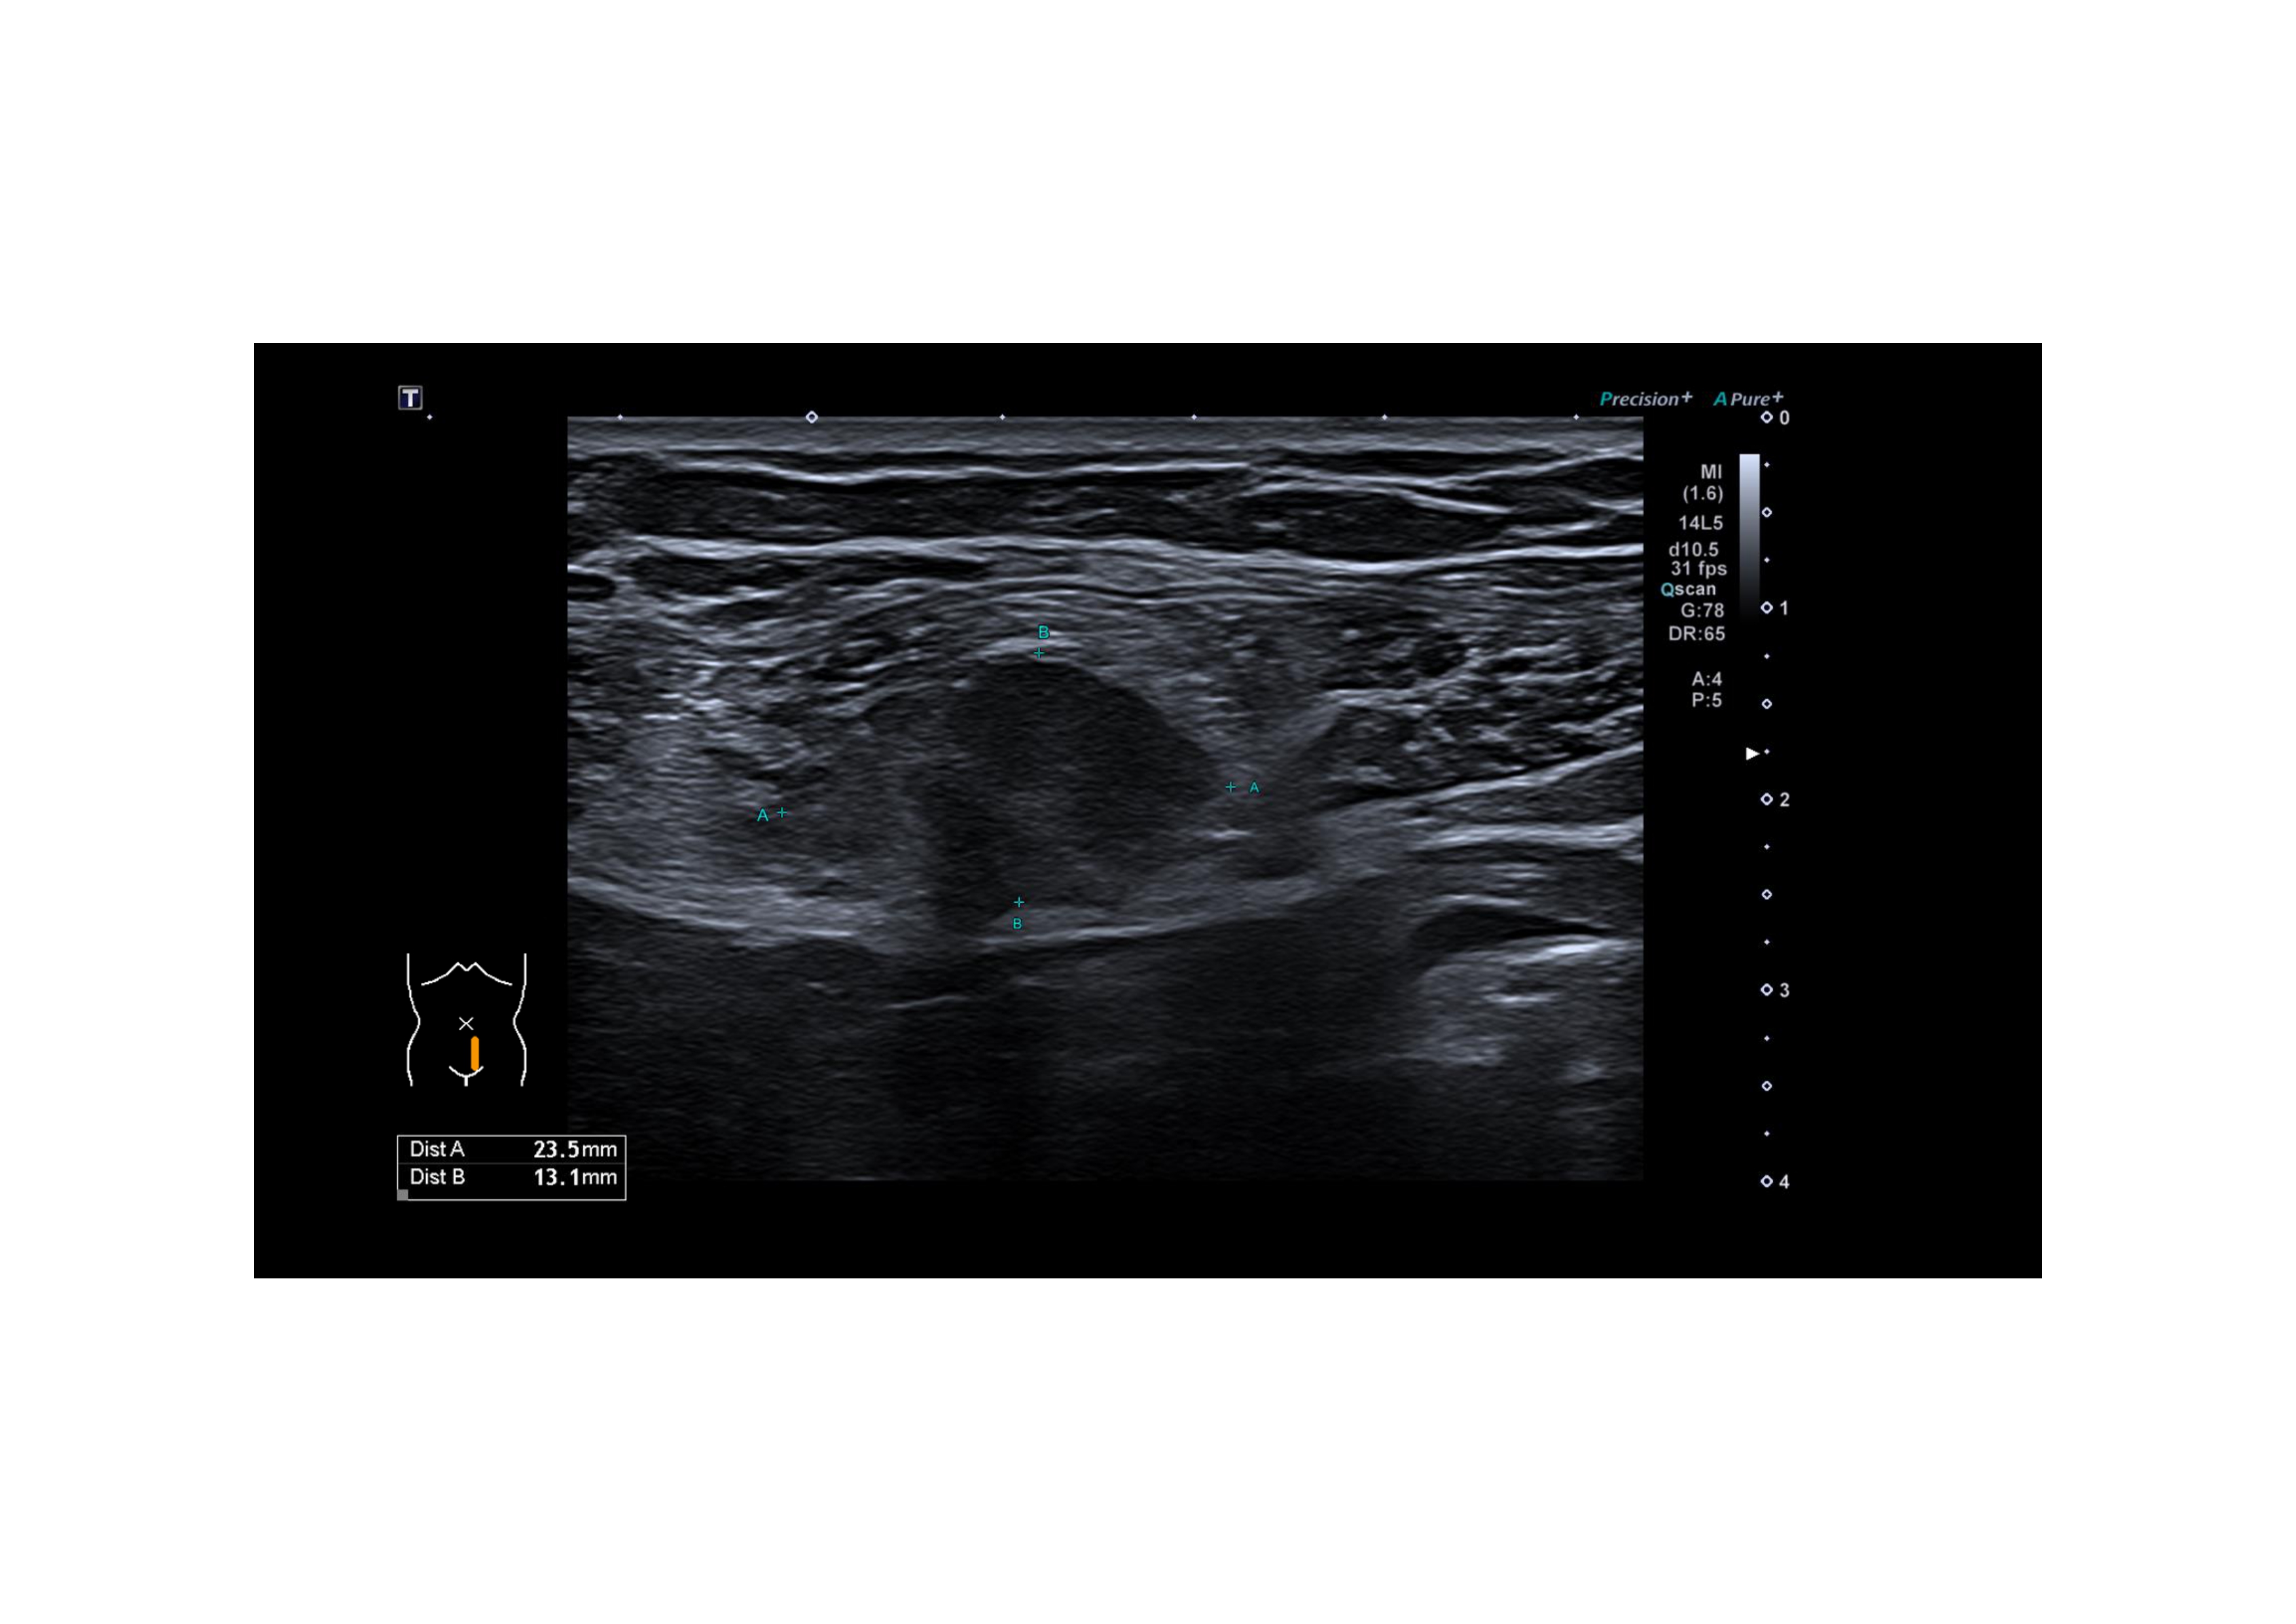

En la exploración abdominal se palpa nódulo doloroso, de 2 cm, adherido a la pared en músculo recto anterior izquierdo, sin cambios con maniobras de Valsalva. No adenopatías inguinales, ni en otras localizaciones. Resto de la exploración física sin hallazgos de interés. Se realiza una ecografía clínica para mejor caracterización de la lesión.

Hallazgos ecográficos

Lesión nodular, de 24 x 13 mm, hipoecogénica con puntos hiperecogénicos internos, márgenes mal definidos, vascularizada, a nivel de musculatura de recto anterior izquierdo sin contactar con cavidad abdominal. Vejiga, no valorable, sin hallazgos de interés.